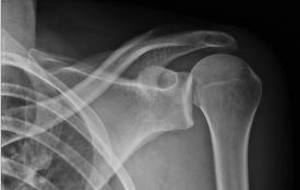

Guillaume Cuffel est victime d'une luxation de l'épaule, avec arrachement des ligaments (blessure identique à celle de Côme Lecossais il y a 15 jours).

Il a une luxation acromio-claviculaire complète... Pour résumer, les ligaments qui retiennent la clavicule à l'omoplate ont "sauté"!!!

Il s'est fait poser 2 broches... Entre la rémission, et la ré-éducation, il ne va pas pouvoir jouer avant... ... longtemps